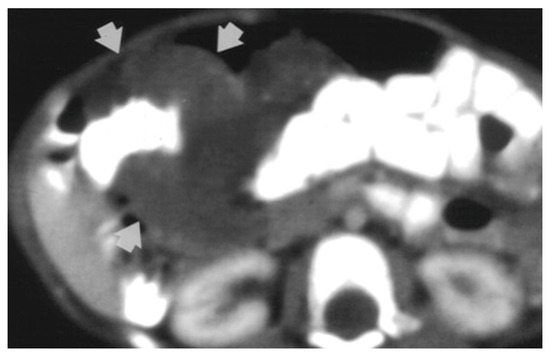

2. Detailed Case Description